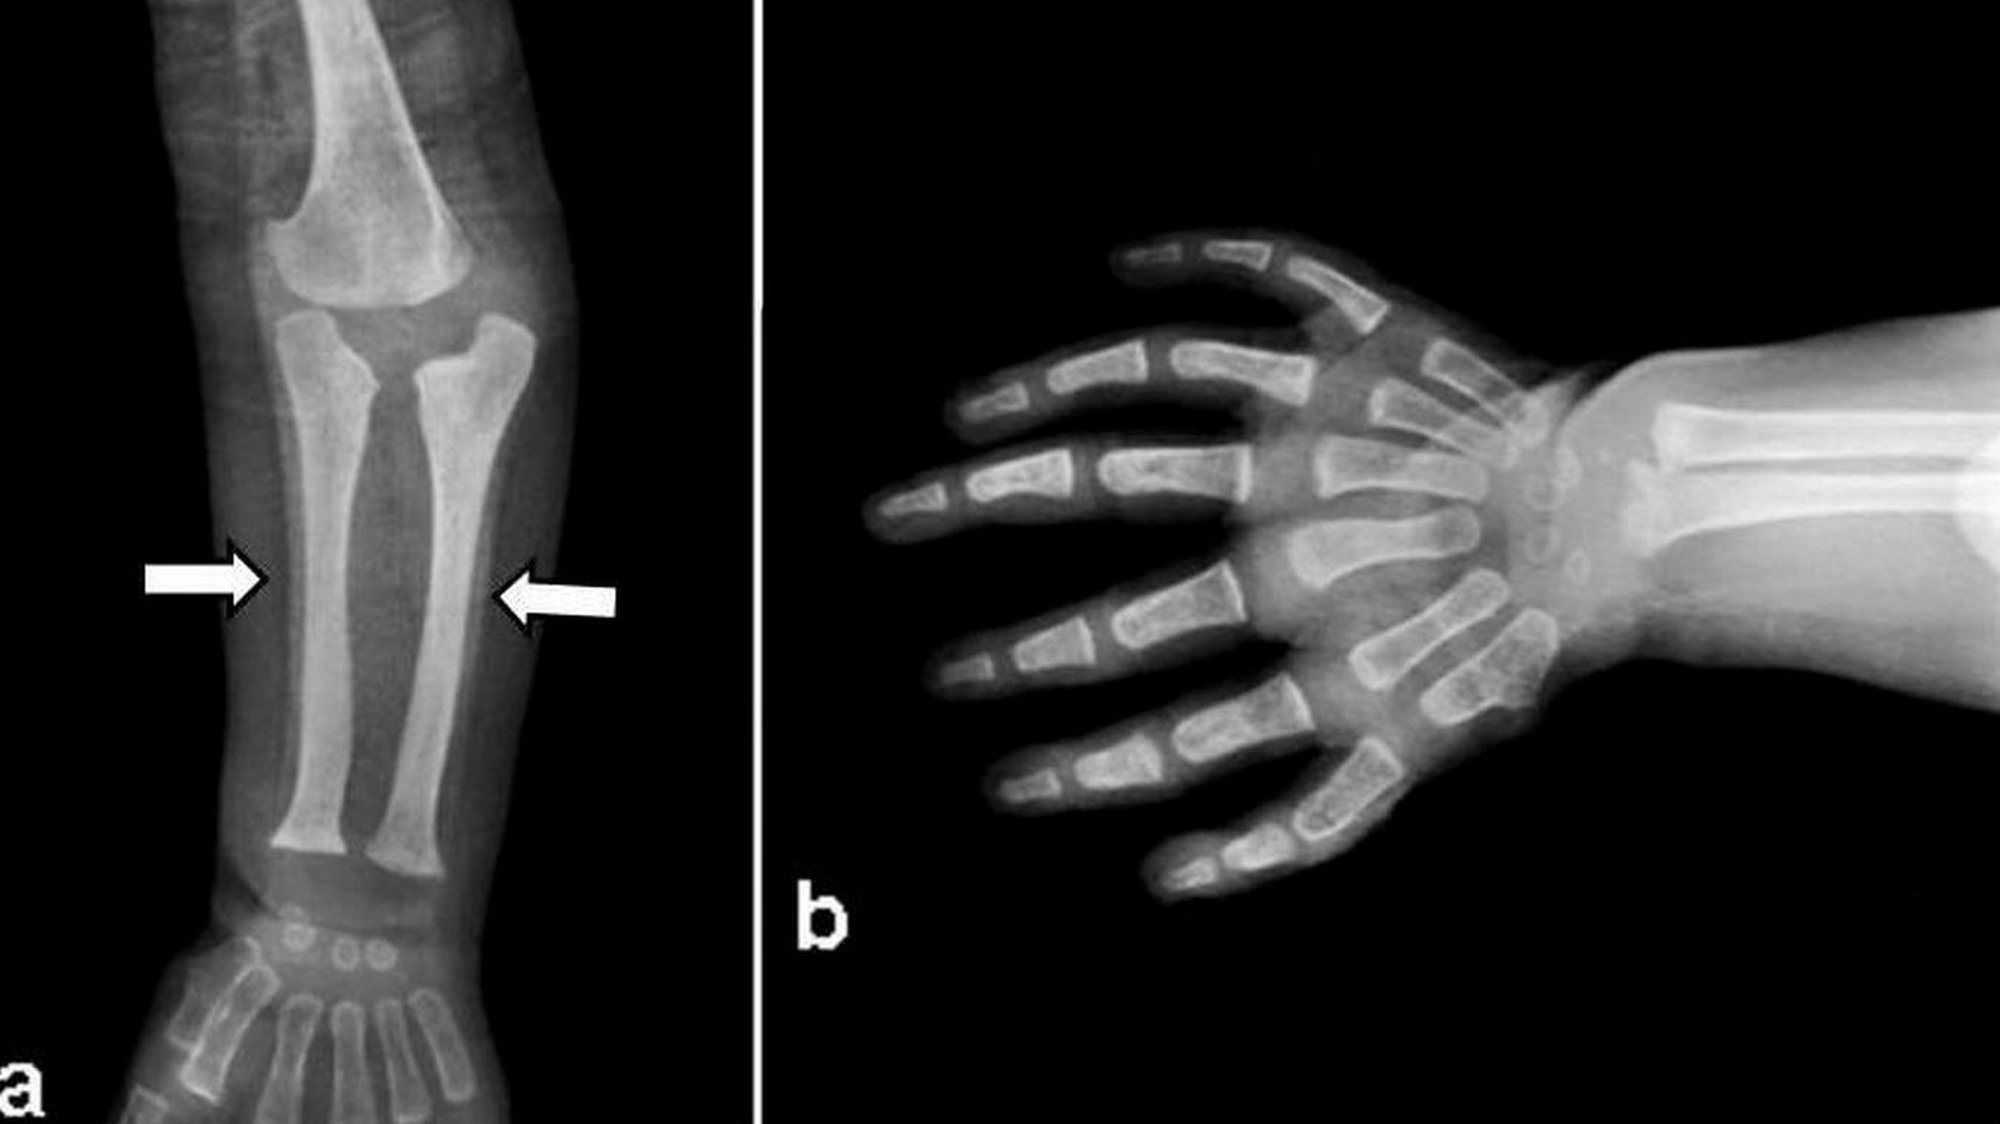

Bu gördüğünüz, "ulnar dimelia" adı verilen ve yaygın olarak "ayna el sendromu" olarak bilinen, nadir görülen kalıtsal hastalığa ait bir X-ray taraması görüntüsüdür. Bu hastalığa sahip kişilerin işaret parmakları ile başparmakları bulunmaz; bunun yerine diğer üç parmakları ayna simetrisine uygun bir şekilde çiftlenmiştir. Kişilerin ellerinin ayna görüntüsündeki parmaklar tam gelişmiş ve işlevseldir.

Hastalık, el ve kol gibi uzuvlarda gelişimsel anomaliler ve yamukluklar şeklinde kendini gösterir. Buna bağlı olarak bilekte de sertlik ve katılaşma görülebilir. Uzuvlardaki yamulma, kemiklerde meydana gelen uzunluk farklarına bağlı olarak yaşanır.